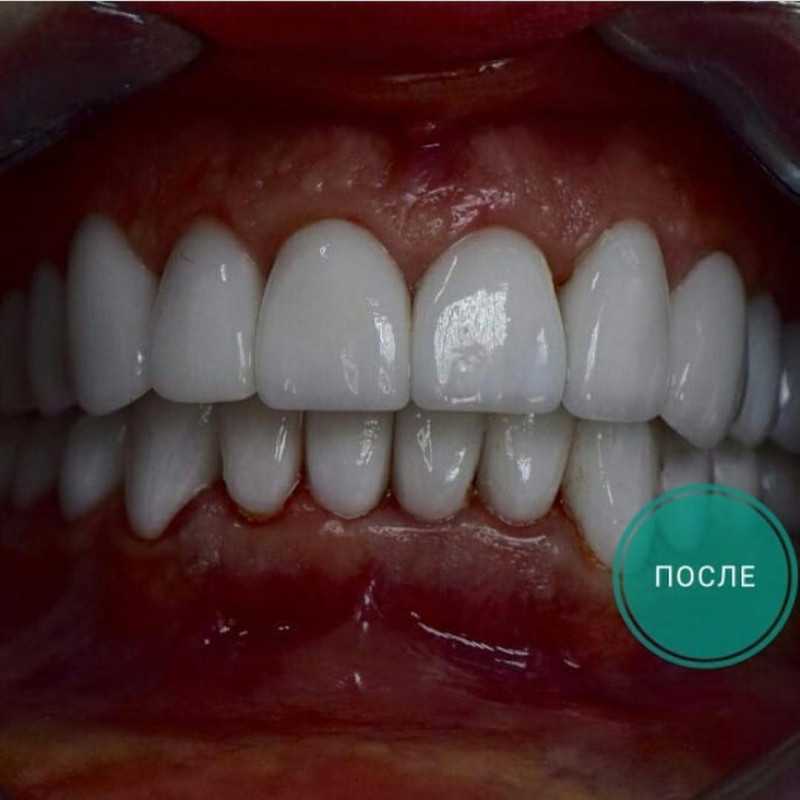

Фотографии до и после: Установка коронки на зуб

На странице представлено портфолио стоматологий Краснодара с фото работ до и после установки зубных коронок. Показываем, как можно полностью восстановить форму разрушенного зуба и эстетичный вид улыбки. На странице собраны разные клинические случаи восстановления одиночными коронками из металлокерамики, циркония или керамики. Изучите результаты до и после процедуры и выберите подходящую клинику для восстановления зуба в Краснодаре.

Установка коронки из диоксида циркония

Пациент обратился с жалобой на эстетику зубов.

РЕШЕНИЕ:

Провели лечение кариеса на 11-м зубе.

Установили четыре циркониевые коронки с 12-го по 22-й зуб.

Во время изготовления коронок

пациенту были изготовлены временные пластмассовые коронки.

Время работы - 10 дней

Доктор: Айрумов Артур Сергеевич